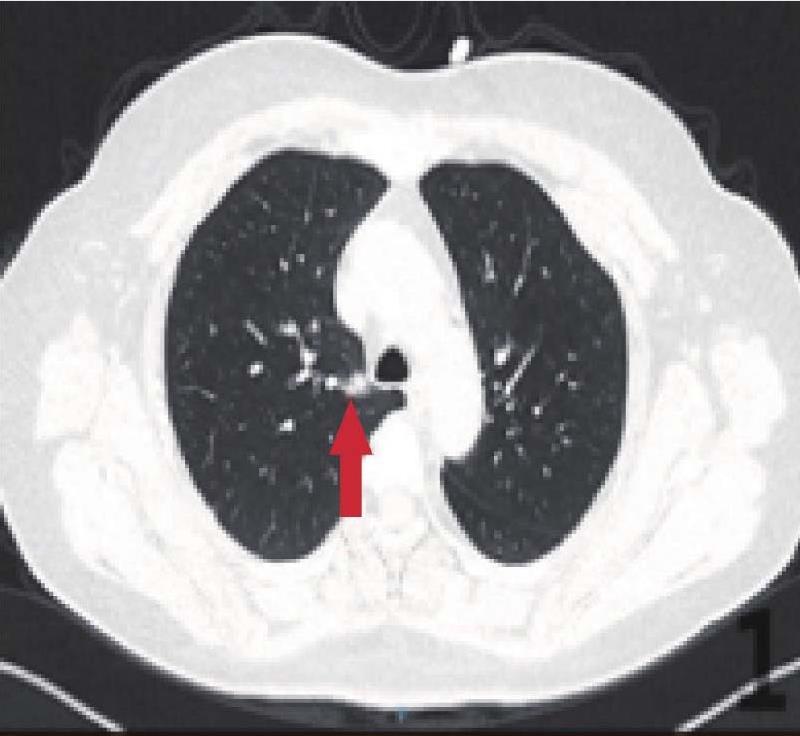

不过肺结节在CT上的形态学表现对判断良性、原发或转移瘤的来源有较强的提示意义。国外有研究发现,近80%~90%的甲状腺癌、肝癌及肾癌的肺转移瘤系光滑球形灶;而喉癌、结肠癌及乳腺癌近60%的转移灶形态都不规则;乳腺癌肺转移多表现为肺内大小不等的多个结节,而表现为单个结节者很少见。实际上,肺转移灶的原发肿瘤以胃、乳腺和肺本身的肿瘤最为常见,而肿瘤在肺的转移是由其他原发肿瘤经淋巴道转移所致,所以肺门和纵隔淋巴结常受累及,且CT表现常为双肺弥漫的粟粒样的结节,以双下肺和周边肺野分布为主,轮廓比较清楚,通常结节不是毛玻璃样的,这些都是转移灶的一些基本特点。